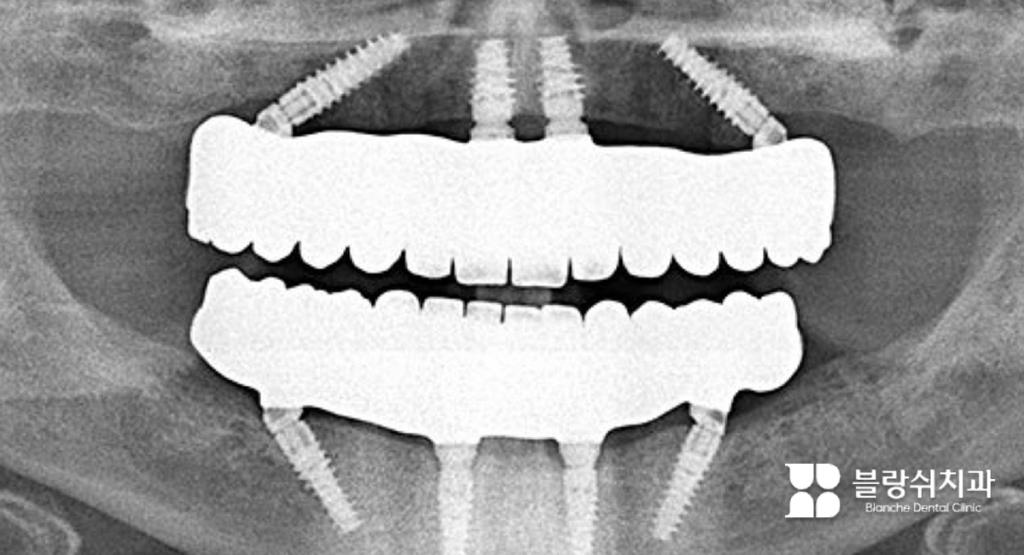

틀니 대신 디지털 풀아치 임플란트로 자신감을 찾으세요(실제 사례)

이 환자분은 20여 년간 틀니를 사용하셨습니다. 임플란트 시술 후 얼굴이 변하지 않을까 많은 고민을 하셨는데요. 특히 틀니를 제거하면 입이 안으로 들어가 보일까 걱정하셨습니다. 하지만 절대 그럴 일이 없다고 안심시켜드리며 디지털 풀아치 임플란트를 설명드렸습니다. 이 방법은 잇몸의 부피감까지 회복해 입술과 인중의 주름까지 개선할 수 있기 때문입니다.

위 사진처럼 그동안 틀니를 썼다는 것을 믿을 수 없을 정도로 얼굴이 좋아지셨습니다. 실제로 수술 이후 “주변에서 10년은 더 젊어 보인다고 해요”라는 말씀을 전해주셨습니다. 충분히 그럴 만합니다.